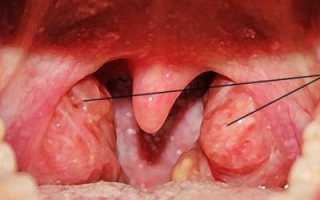

Температура может колебаться от 37,3 до 39 градусов, либо быть в норме. Катаральная ангина может сопровождаться ознобом, судорогами. Небные миндалины увеличиваются, отекают, наблюдается гиперемия дужек слизистой оболочки глотки;

Фолликулярная: характеризуется наличием гнойного воспаления лимфоидных образований глотки (фолликулов) в виде отдельных очагов нагноения на небных, трубных, глоточных или язычных миндалинах, а также увеличенных шейных регионарных лимфоузлов.

Заболевание сопровождается резким повышением температурных показателей, болью в горле, слабостью. Ребенок становится беспокойным, плачет, отказывается от еды, не хочет ничего делать. Можно наблюдать затруднение речи, наличие серого налета на языке;

Лакунарная: проявляется стремительно, характеризуется недомоганием и слабостью, повышением температуры тела до 39 градусов, ознобом, нарушением сна, потерей аппетита, уменьшением активности, неприятными ощущениями в гортани.

Симптомы ангины у детей: воспаление и увеличение лимфоузлов, отек горла, наличие гнойных образований белого или желтого цвета на миндалинах, либо полного покрытия налетом поверхности (одной или обеих миндалин);